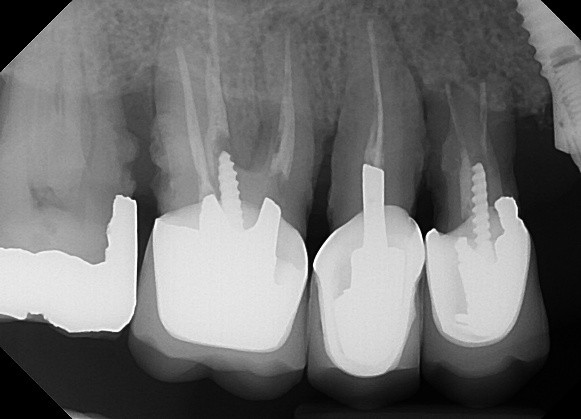

The radiograph shows evidence of

The radiograph shows evidence of calculus on